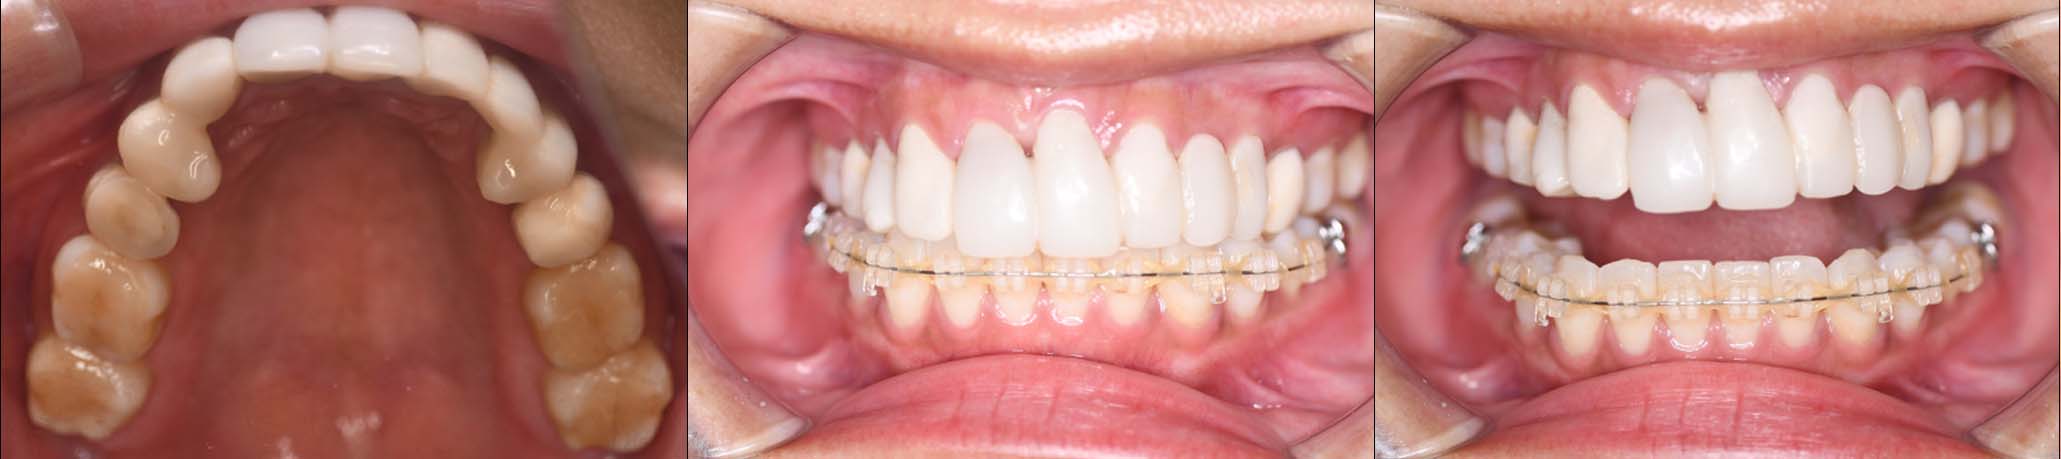

姿勢の変化

2024年 3月 初診時

2024年 10月10日

2025年 12月25日

顔貌の変化